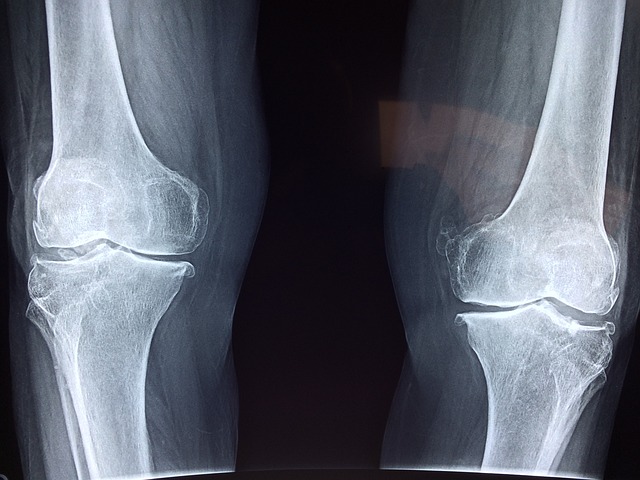

관절염은 관절의 염증과 통증을 동반하는 만성적인 질환으로, 예방과 적절한 관리를 통해 건강한 관절을 유지할 수 있습니다. 이제 관절염의 예방과 관리법, 그리고 자가치료법에 대해 자세히 알아보겠습니다.

관절염 예방, 관리, 자가치료법 관절염의 예방